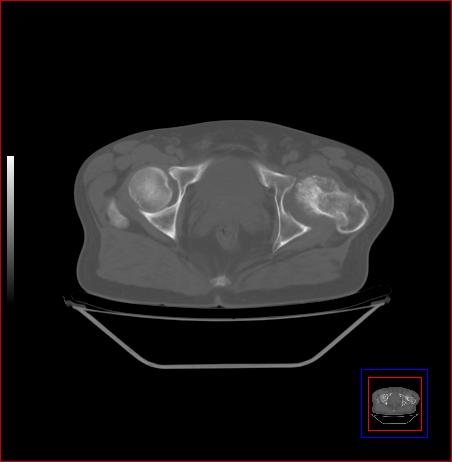

标题: CT15143:髋关节结核?

男,49,髋关节疼痛1年,无肺结核。

骨质破坏,硬化,周围软组织脓肿,支持骨结核

骨质破坏,硬化,周围软组织脓肿,关节间隙增宽,支持骨结核

骨质破坏,硬化,周围软组织脓肿,关节间隙增宽,支持骨结核 .应与无菌坏死鉴别